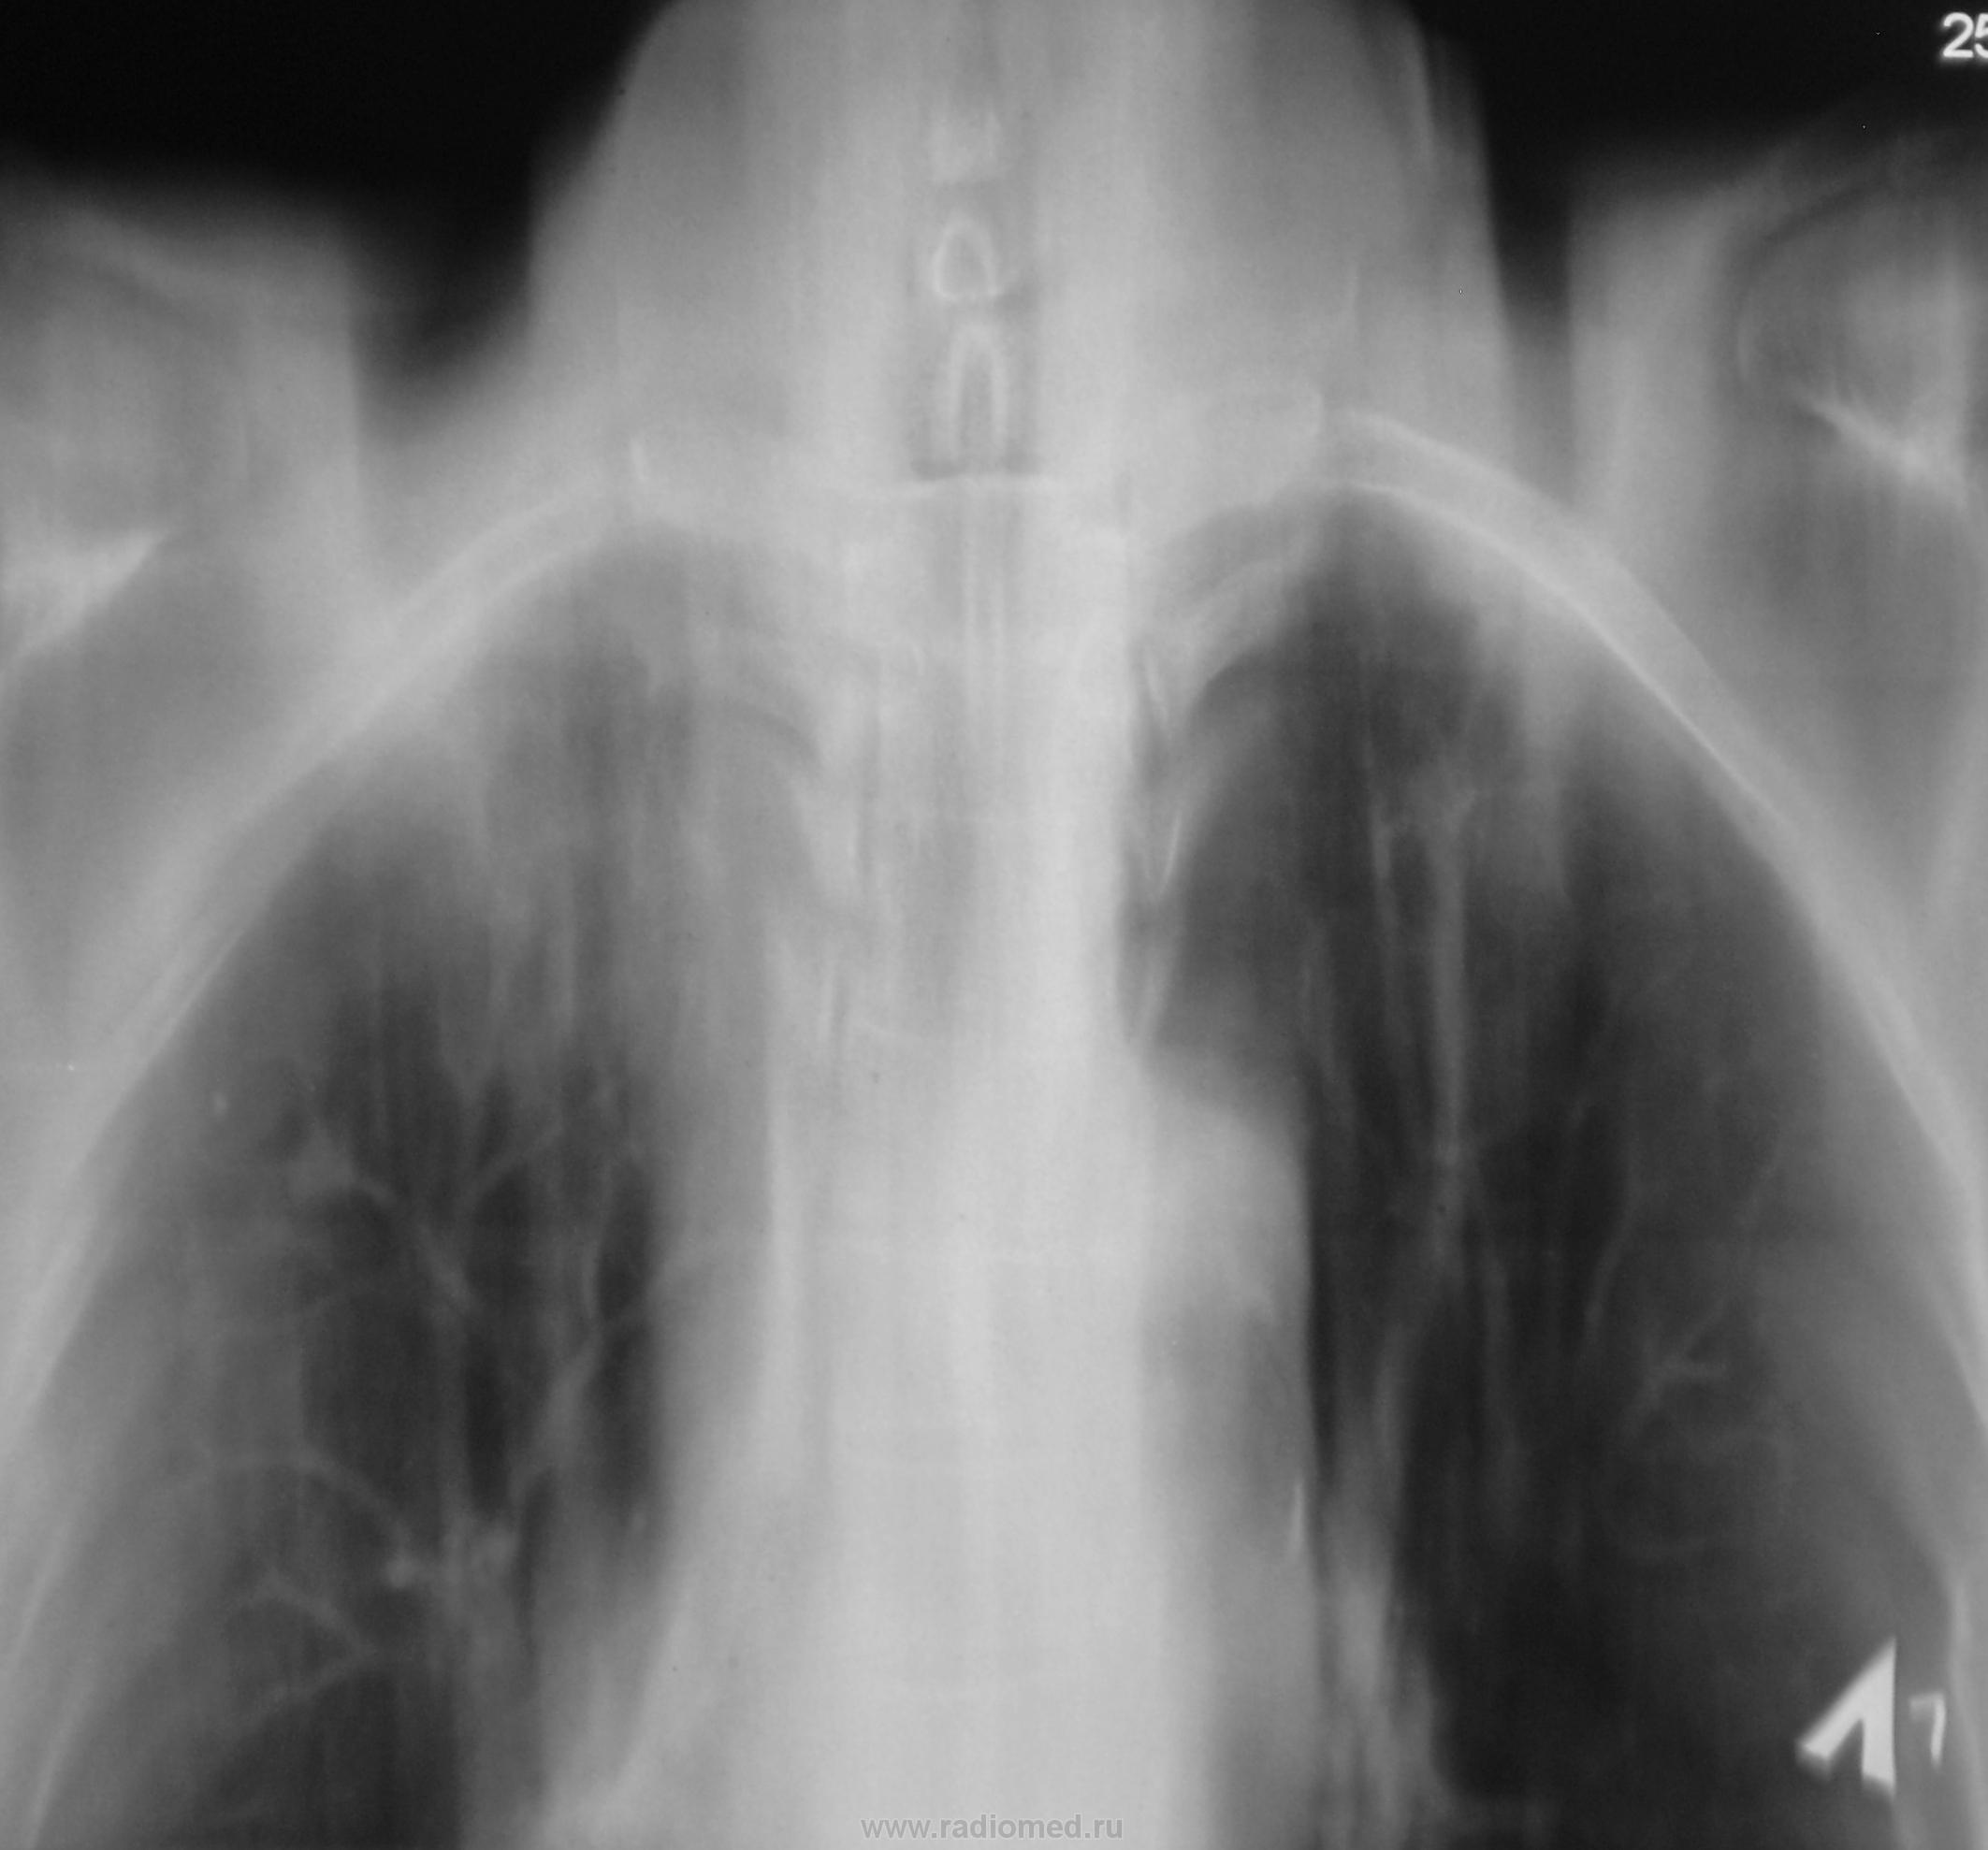

И, еще через год.

История "жизни". Спасибо за показательный случай.

А где же первичный очаг?

Первичный очаг чего?

Мелькнула мысль о метастазах...погорячился ...

У нас с коллегой фтизиатром тоже такая мысль мелькнула.

И как же Вы ее отвергли?